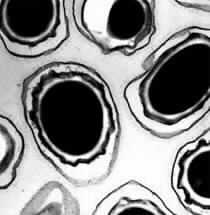

The U.S. Postal Service shut down 11 postal facilities in the Washington area late on Thursday after preliminary tests indicated possible anthrax at a U.S. Navy mail handling center, officials said. The Navy closed the automated mail handling operation at its naval air station in Washington on Thursday to run additional tests after sensors detected traces of a substance that could be anthrax, a Navy spokeswoman said. The substance was identified late on Wednesday by equipment that routinely samples the air in the facility and preliminary tests indicated that it could possibly be anthrax, a deadly bacterial disease, Lt. Corey Schultz said. More definitive testing was underway, she added. "Almost all the mail that's processed there is irradiated, so it's likely the substance would be inactive," Schultz said. She also noted that it was "very unlikely" that the few people who work in the facility were at risk of exposure, but said that they were being evaluated as a precautionary measure. As a precaution, the U.S. Postal Service closed 11 facilities that were serviced by the same contractor that transported mail to the Navy center, a spokesman said. "Out of an abundance of caution we want to make sure we've covered everything," spokesman Mark Saunders said. "We learned late Thursday the Navy test was positive and that more samples were being taken at the facility." Saunders said that the Postal Service would also test its closed facilities. The shutdown affects about 1,500 postal employees. They were being asked to report to their job locations on Friday and would be directed to other centers, Saunders said. In 2001 a series of anthrax attacks, which spanned the East Coast from Florida to Connecticut, killed at least five people, including two Washington postal workers. Letters containing anthrax spores were mailed to news media offices in New York and Florida and anthrax-laced letters were sent to the Washington offices of two senators. Since the anthrax attacks, the Postal Service has spent millions of dollars to test and install equipment to sterilize mail. Anthrax is a bacteria that causes disease in livestock and in humans who have contact with animals. It is considered the No.1 threat for a biological weapon because it is deadly and the bacteria form spores that are hard to kill. **PHOTO CAPTION*** Microscope view of bacillus anthrax spores. Two years after anthrax attacks terrorized the United States, lawmakers in Congress introduced a bill to compensate the victims, many of whom continue to suffer debilitating health problems from their exposure to the potentially lethal bacteria. (AFP/File)